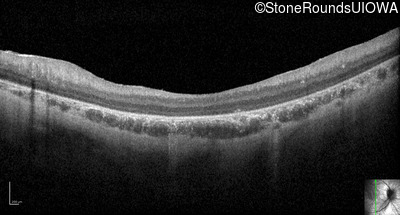

Optical Coherence Tomography - Left - 10/350 sc

Exemplar / OCT Stack